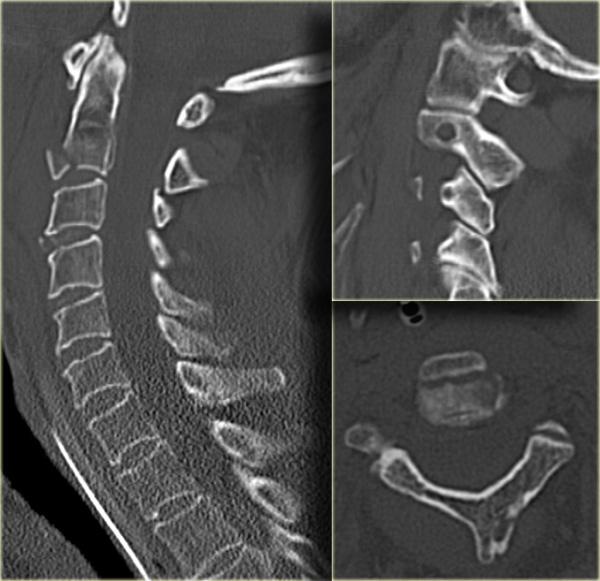

Hình bên trái là hình ảnh của một hành khách 26 tuổi không thắt dây an toàn trong vụ tai nạn giao thông, bị văng ra khỏi xe.

Bệnh nhân có nhiều tổn thương bao gồm tụ máu dưới màng cứng, tràn máu màng phổi, chảy máu ngoài màng cứng tủy sống, gãy cột sống ngực, gãy mỏm ngang L3 trái và gãy xương đòn trái.

Không có thiếu hụt thần kinh khi khám thực thể.

Các phát hiện bao gồm:

- Gãy qua nền mỏm răng

- Phù nề phần mềm trước cột sống

- Đứt dây chằng gian gai C1-C2

- Không quan sát được cột sống cổ thấp

CT xác nhận các phát hiện trên X-quang và cho thấy thêm hai phát hiện bổ sung:

- Hình ảnh qua phần bên của C2 cho thấy rõ ràng đường gãy đi qua thân C2, tức là gãy mỏm răng loại III.

-

Màng cứng phía sau ở vị trí bình thường, nhưng màng cứng phía trước bị di lệch (mũi tên).